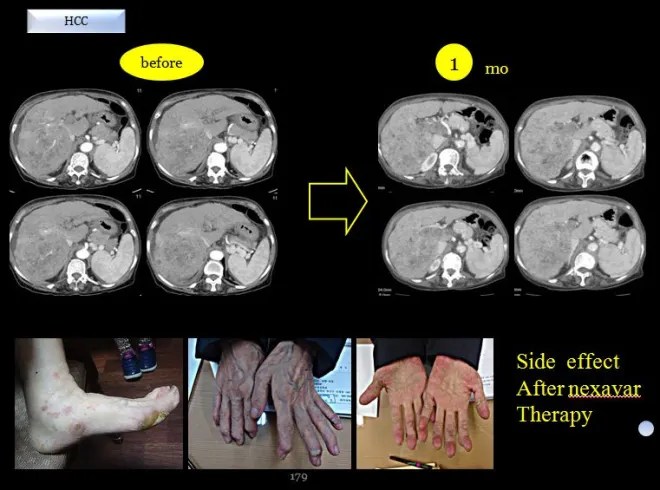

이 환자는 태음인으로 연세가 꽤 있는 분이었다. 간암 말기로 발견이 되어서 우측간엽이 거의 다 암으로 퍼져 있어서 색전술도 불가하고 넥사바를 사용하였다. 내가 보기로는 넥사바가 태음인 약물인데도 불구하고 피부에 대한 부작용이 너무 심해서 한 달도 채 못먹고 포기를 하였다.

이후에 협진하는 병원의 선생님이 체질 분류를 원해서 몇몇 태음인들을 분류해 주었는데 넥사바 사용으로 매우 좋은 결과를 가져왔다는 이야기를 들었다. 하지만 이분은 피부 손발에 부작용이 심해서 사용치 못하고 중단하고 내원하였다.

위에서 보듯이 한 달여 넥사바 사용 후에 종양은 더욱 진전이 되고 손발의 허물은 다 벗겨졌다. 이분은 70세가 넘는 분이었고 당시 복수흉수가 모두 심하게 차 있어서 내 생각으로는 얼마 못 가시리라 생각하였다.